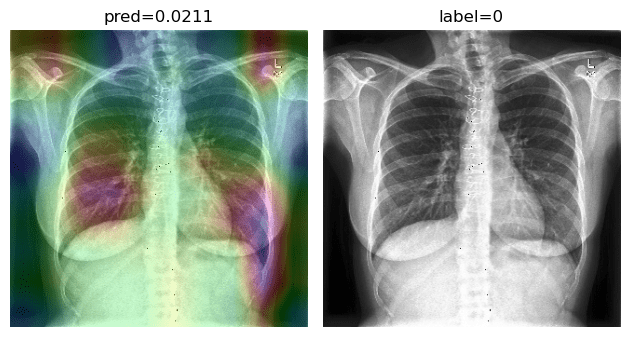

Accuracy score is 81.04%, with f-scores of 0.85 and 0.76 for CP and CAP classes, respectively. In a number of cases, especially in the first stages of virus progression, CP has unilateral findings. Also, CAP may cause bilateral consolidations. Therefore, some cases are expected to be misclassified between CP and CAP. From the confusion matrix, it could be seen that a relatively high number of images are misclassified between CAP and normal. A potential reason for this issue is considered to be related to wrong labeling. Besides, some CAP CXRs are from patients with early-stage disease development. To confirm the model performance, Grad-CAMs are plotted in Fig. 19.

Refer to caption

Figure 19: COVID-CXNet multiclass classification visualization results

The model is properly looking at one lobe for detecting CAP and both lobes for CAP and normal images. There are some wrong labels, nevertheless. A figure containing more visualizations is found in Appendix C. To further enhance statistical scores, a hierarchical approach is implemented. In the first level, we classify images into normal and pneumonia classes. In the second level, pneumonia images are categorized into CP and CAP. Final confusion matrix is illustrated in Table 5.